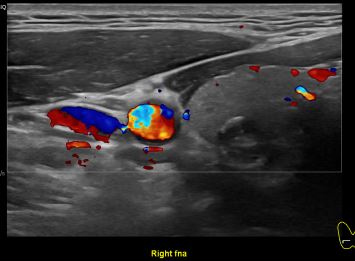

상기환자 외부검사이상 세침검사위해 내원하신 30대후반 여성분으로

의심스러운 갑상선 우엽 결절 세포검사 진행후 갑상선암으로 진단되었습니다